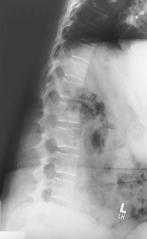

Swimmer’s (Twining Method) C5-T3 Region

• Erect preferred, align C-spine to CR (and centerline of IR).

• Elevate arm and shoulder closest to IR and rotate this shoulder slightly anteriorly or posteriorly.

• Opposite arm down, relax and depress shoulder, with slight opposite rotation (from other shoulder) to separate humeral heads from vertebra. May also be taken in lateral recumbent position with one arm and shoulder down and one up—Pawlow method.